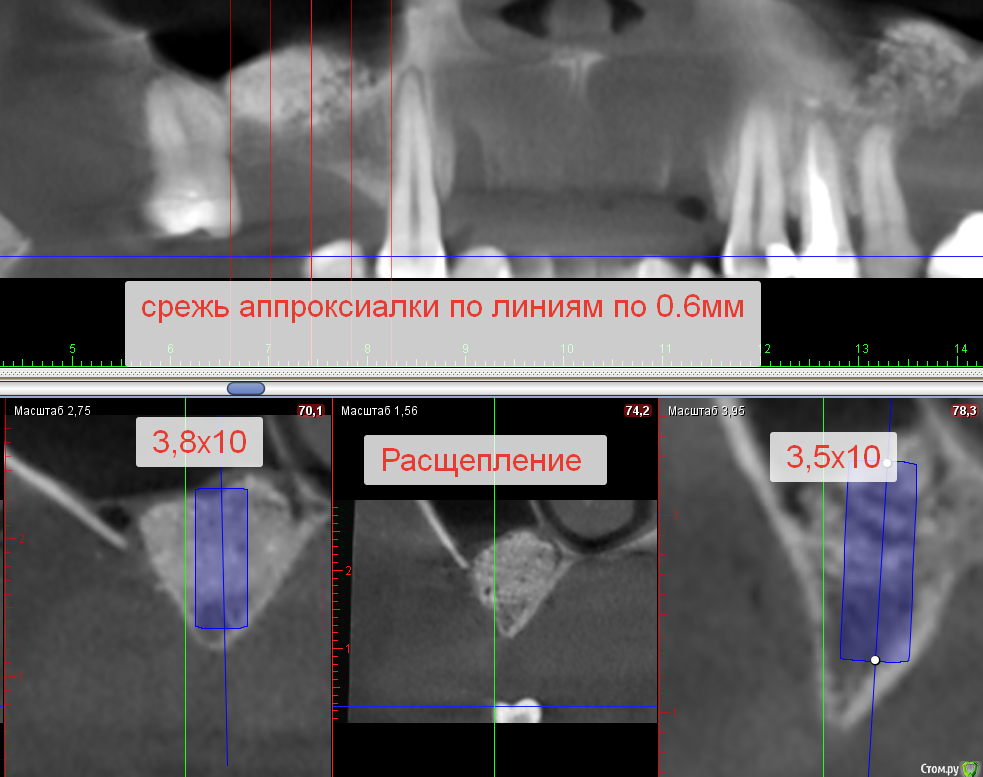

Sergiosse Опубликовано 23 мая, 2019 Поделиться Опубликовано 23 мая, 2019 (изменено) 6 месяцев назад пациентке был проведён ОСЛ. Подошло время устанавливать импланты. Ширины кости недостаточно, сижу и думаю а можно ли сделать в этой области расщепление. Какие могут быть риски? Не оторвется Графт от кости ? Изменено 23 мая, 2019 пользователем Sergiosse Ссылка на комментарий

kramer Опубликовано 23 мая, 2019 Поделиться Опубликовано 23 мая, 2019 Да вроде достаточно ширины 2 Ссылка на комментарий

Дмитрий Л. Опубликовано 25 мая, 2019 Поделиться Опубликовано 25 мая, 2019 Возможен раскол графта( Ссылка на комментарий

vgraev Опубликовано 21 июня, 2019 Поделиться Опубликовано 21 июня, 2019 расколется графт )) там же без проблем можно и так поставить, субкрестально на 1.5-2 мм и можно пошире импл 4.0 или 4.5. скорее всего на одну или две последних фрезы не надо будет проходить чтоб торк получить Ссылка на комментарий